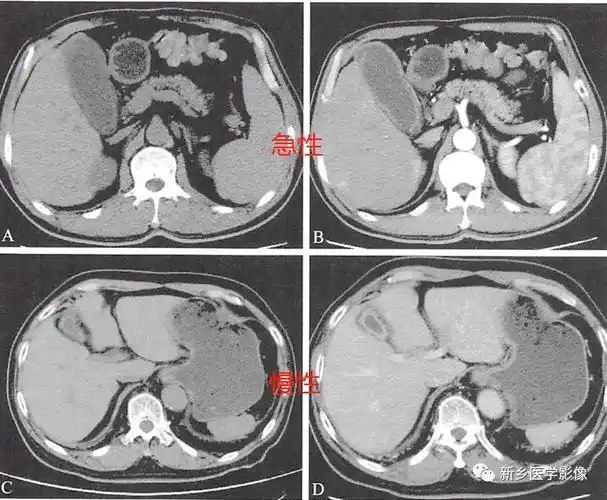

读书笔记胆囊炎胆囊息肉胆道结石ct分析